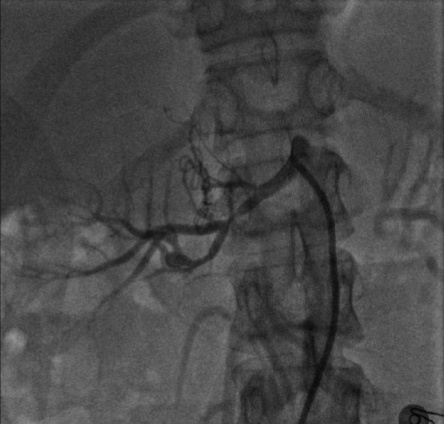

年轻女性,重度高血压伴低血钾

病史摘要:患者为 21 岁女性,1 天前因头晕测血压发现重度升高,无其他不适。1 个月前有上呼吸道感染症状,后出现颌下淋巴结肿大。既往体健,无慢性疾病、传染病、手术外伤等病史,月经规律。家族中外祖母有高血压,否认一级亲属高血压及其他遗传性疾病史。 诊疗过程:入院查体无明显异常体征。辅助检查提示血钾低,醛固酮、肾素活性增高,尿蛋白微量。肾脏、肾上腺等超声部分未见明显异常,眼底为 I

右肾动脉狭窄

肾血管性高血压